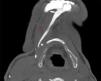

A bone scan was performed, showing localized technetium uptake in the mandible. An axial minimum intensity projection CT scan of the neck (MIP) (Fig. 1) and a 3D reconstruction (Fig. 2) were subsequently performed, showing an abnormal calcification linear stretching from the lower border of the mandible to the hyoid, following the anterior digastric muscle.